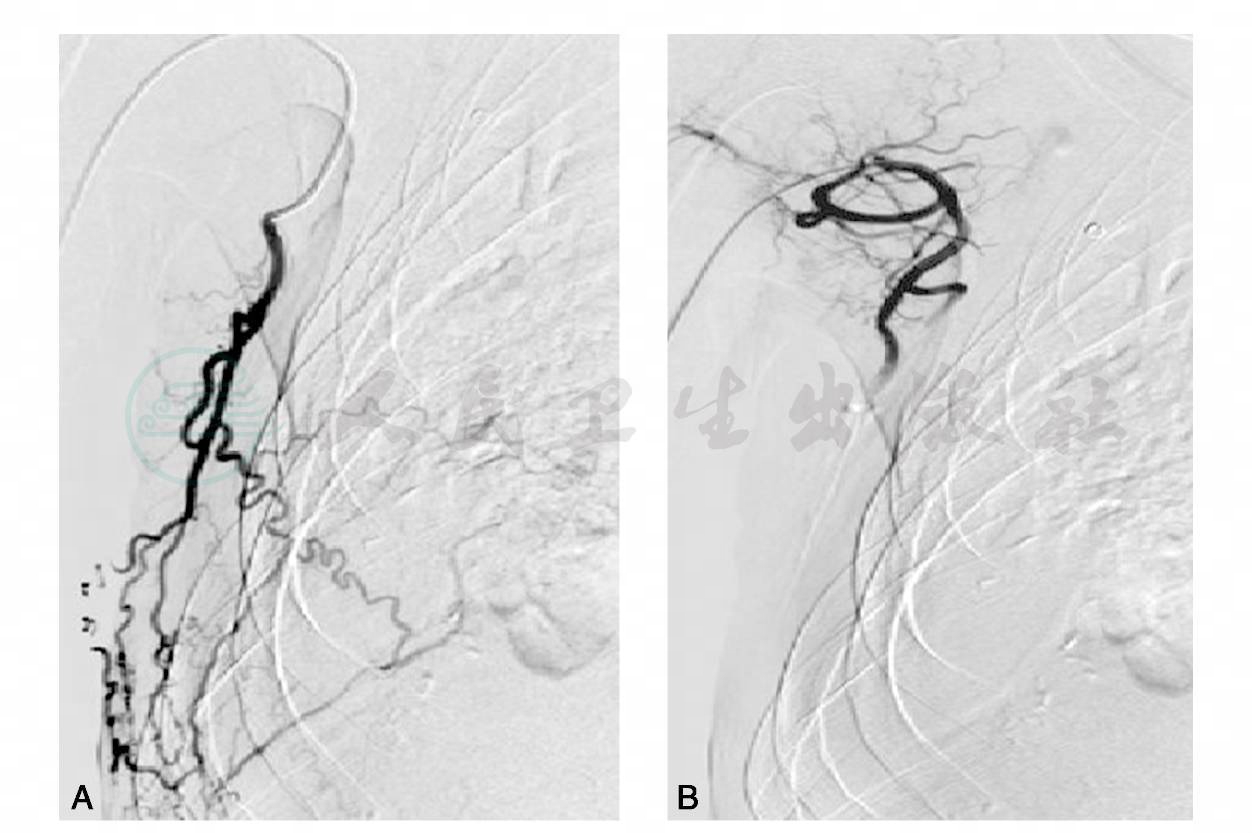

16小时后,患者再次咯鲜红色血液约300ml,余症状、体征基本同前。考虑患者咯血量较多,鲜红色,再急诊行支气管动脉栓塞术,此次手术从右肱动脉入路,将Crobra导管行至右锁骨下动脉开口处,造影示右胸廓内动脉、胸廓外动脉、腋动脉及多支小动脉扩张迂曲,与肺静脉相通(图3)。

图3 右锁骨下动脉造影示右胸廓内动脉、胸廓外动脉、腋动脉及多支小动脉扩张迂曲,与肺静脉相通

分别用Crobra导管及Sp导管超选择供血动脉栓塞,共使用明胶海绵4片及3cm- 3mm钢圈2个(图4~9;图A、图B分别为栓塞前、后),术毕,安返病房。术后患者咯血消失,偶有发热,考虑与栓塞有关,给予抗炎治疗,病情完全好转后出院。随诊10个月患者未出现咯血,后患者死于脑膜转移瘤。